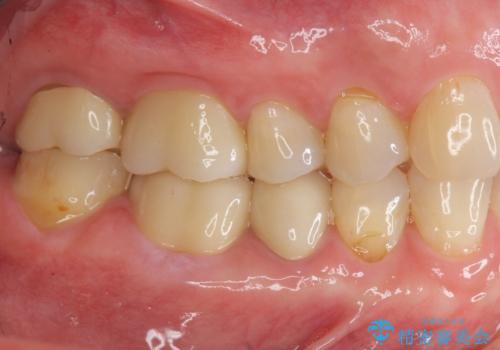

治療後、明るくなった口腔内を見て大変満足いただくことができました。

色調だけでなく、精密な治療を行うことで虫歯の再発の確率を下げることも可能になります。